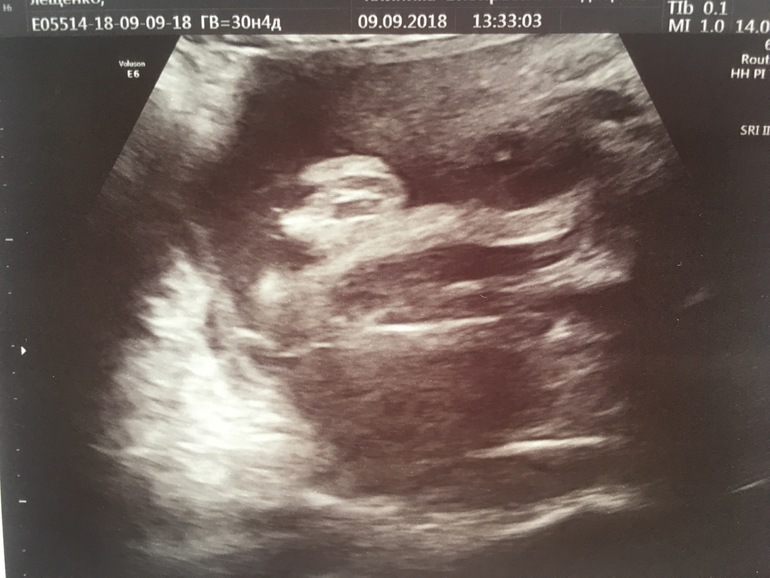

Мне примерно на этом сроке первый раз сказали, что девчонка) как видишь, не ошиблись!

Так из-под попки угол наклона бугорка будет совсем не определить. Потому и смотрят так, как снизу прикрепили фото 👇🏻

Это я понимаю) просто мне интересно как выглядит девочка снизу если смотреть, потому что нам только показали снизу, уровень наклона не удалось посмотреть. Очень активный человек у нас там)